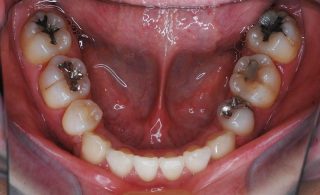

スピード矯正のケースです。

他院で3年以上矯正装置をつけていないとダメという診断で、スピード矯正を希望して来院。3年が半分になれば良いとのことでしたので、スピード矯正対応となりました。ワイヤーの治療期間は、当院では1年3か月でした。患者様からもあっという間の矯正治療でしたと満足のお言葉をいただきました。時間がない方は、是非お試し下さい・・・スピード矯正。通常の矯正より確実に早いです。

- ①治療期間:1年3カ月(約30回)

- ②費用:約115万円(税別)